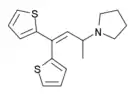

The pharmacodynamic response to an opioid depends upon the receptor to which it binds, its affinity for that receptor, and whether the opioid is an agonist or an antagonist. For example, the supraspinal analgesic properties of the opioid agonist morphine are mediated by activation of the μ1 receptor; respiratory depression and physical dependence by the μ2 receptor; and sedation and spinal analgesia by the κ receptor. Each group of opioid receptors elicits a distinct set of neurological responses, with the receptor subtypes (such as μ1 and μ2 for example) providing even more [measurably] specific responses. Unique to each opioid is its distinct binding affinity to the various classes of opioid receptors (e.g. the μ, κ, and δ opioid receptors are activated at different magnitudes according to the specific receptor binding affinities of the opioid). For example, the opiate alkaloid morphine exhibits high-affinity binding to the μ-opioid receptor, while ketazocine exhibits high affinity to ĸ receptors. It is this combinatorial mechanism that allows for such a wide class of opioids and molecular designs to exist, each with its own unique effect profile. Their individual molecular structure is also responsible for their different duration of action, whereby metabolic breakdown (such as N-dealkylation) is responsible for opioid metabolism.

There are a number of broad classes of opioids:[260]

Tramadol and tapentadol, which act as monoamine uptake inhibitors also act as mild and potent agonists (respectively) of the μ-opioid receptor.[264] Both drugs produce analgesia even when naloxone, an opioid antagonist, is administered.[265]